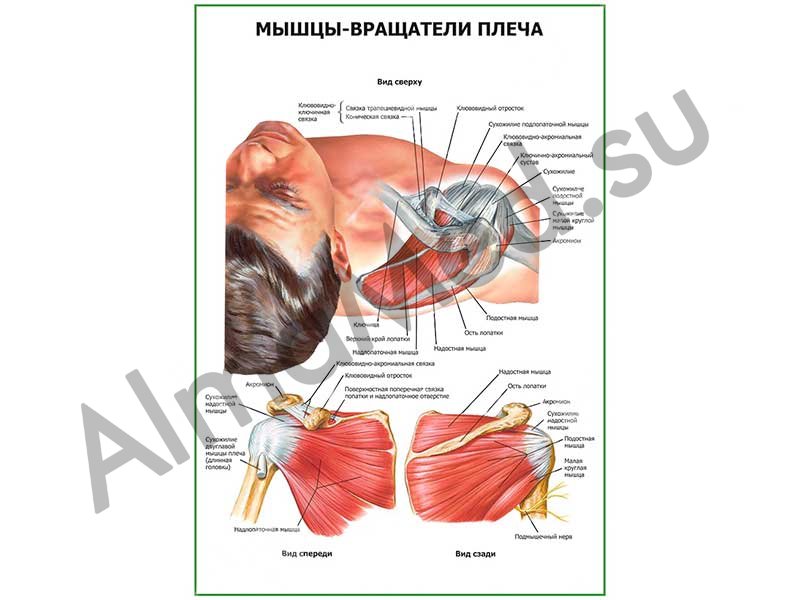

Фотографии мышц ротаторной манжеты плеча